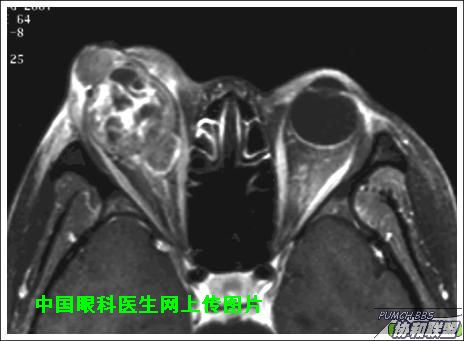

出院后半年发现右眼出现肿物,增长较快,随来京再次就诊(图1),转来我科。门诊检查发现:右眼无光感,结膜下肿物,突出睑裂。眼球突出,上移位。眶外侧可触及硬性肿物。超声(图2),CT(图3),MRI(图4,5,6)显示如图.

再询问病史,患者最初就诊前曾在当地怀疑“纵膈肿瘤”,未做手术,仅做化疗及放疗,后诊断不清。最近胸片正常。